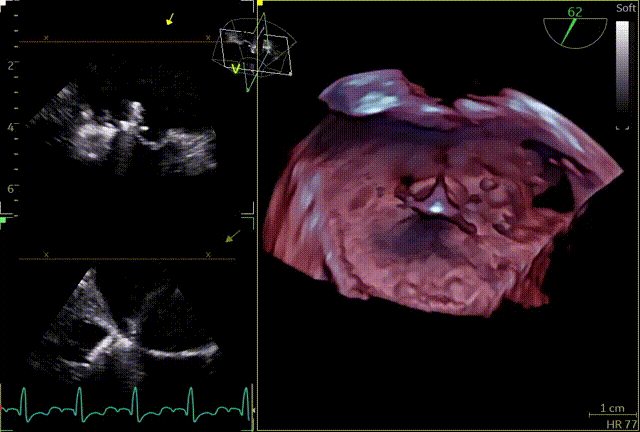

术前TEE及左房压

1区

1区带彩

2区

2区带彩

3区

3区带彩

3D

3D带彩

术前肺静脉频谱

3区gap

术前左房压